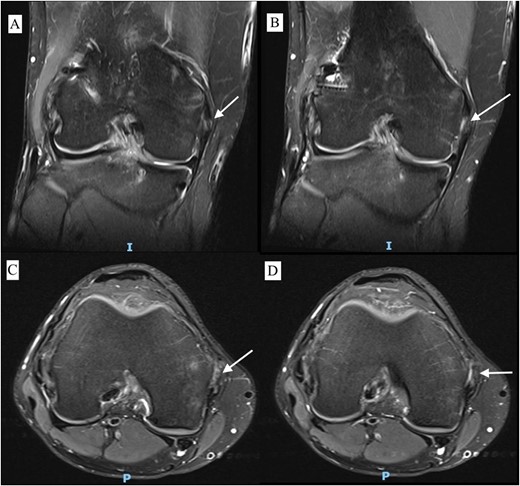

A 23-year-old male veterinarian presented to our out-patient department postright ACL reconstruction with hamstring autograft, PHMM tear by all-inside repair via sMCL pie-crusting technique, and lateral extra-articular tenodesis (modified Lemaire) in June 2023. A preoperative plain radiograph of the right knee revealed no evidence of HO (Fig. 1). No evidence of heterotopic ossification was detected in the right knee on plain radiographs taken 2 weeks postsurgery. (Fig. 2). Five months postsurgery, plain radiographs revealed new bone formation at the medial femoral condyle, precisely where the sMCL femoral origin was located (Fig. 3). The patient was asymptomatic and continued with rehabilitation. Seven months after the surgery, the patient started to complain of pain and clicking sensations when the right knee was flexed beyond an angle of 130°. Magnetic resonance imaging revealed consolidation of the newly formed bone, leading to a diagnosis of HO post-sMCL pie-crusting (Fig. 4). Nine months following surgery, the patient began to feel a bony mass on the medial side of the right knee. A plain radiograph and computed tomography (CT) scan revealed the complete formation of a bone island (Fig. 5). The past surgical history of this patient revealed that he had undergone left knee ACL reconstruction with hamstring autograft in December 2021, which failed and was complicated by a PHMM tear. The patient had presented to our facility for a revision. A revision ACL reconstruction was done using a bone-tendon-bone (BTB) autograft and PHMM tear all-inside repair via the sMCL pie-crusting technique in February 2022. A 2-year follow-up of the left knee, including physical examination and 3D-CT scans (Fig. 6), revealed no symptoms or signs of HO, although the same technique of sMCL pie-crusting was employed. Our patient suffered no head trauma during treatment. Past medical, drug, allergy, family, social histories, and reviews of systems were irrelevant to our case.

MRI T2 weighted image of right knee with different sections of coronal view (A, B) and axial view (C, D) 7 months postoperative showing HO.